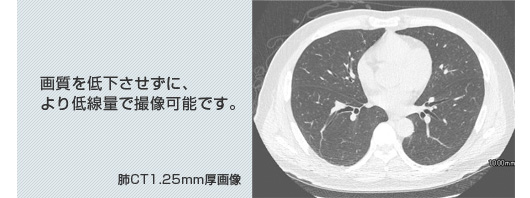

64列マルチスライスCT「Optima CT660Pro」 導入

<肺CT・内臓脂肪測定CT検査使用装置>

少ない線量で高画質の画像診断情報を提供します

●息止め時間短縮(肺:約4秒)

●最新の技術でより低線量を実現(当院従来比:最大50%減)

●精密検査並みの画像取得可能(スライス厚:1.25mm)

GE製マルチスライスCT Optima CT660 Pro(64列CT)

肺CT1.25mm厚画像 画質を低下させずに、より低線量で撮像可能です。